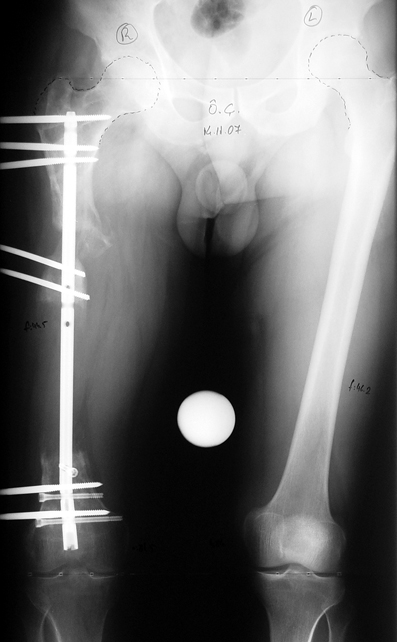

Vaka 1

Vaka 2